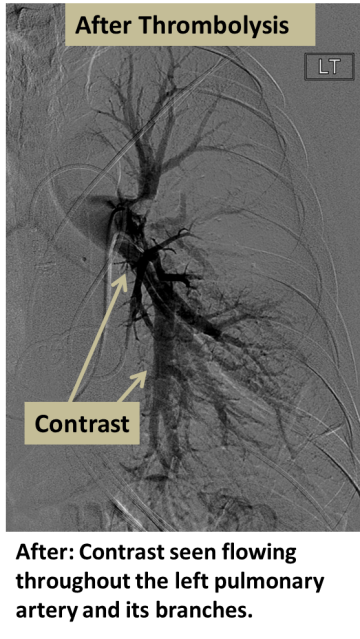

After: Contrast seen flowing throughout the left pulmonary artery and its branches